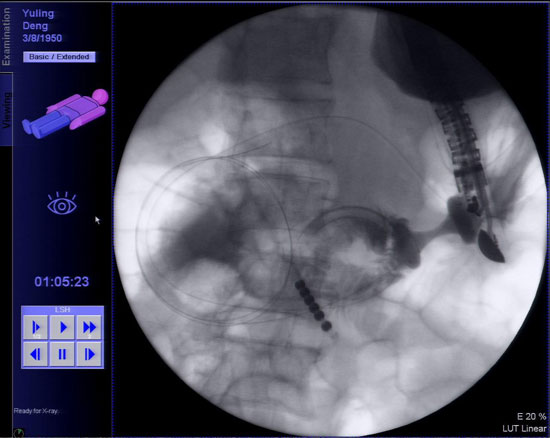

经过术前准备,3月7日下午患者被送入内镜诊疗中心,术中在X线透视下胡锦华副主任医师将双球囊送入空肠固定屈氏韧带附近肠管,在超声内镜引导下经胃腔穿刺肠壁置入导丝,沿导丝放置双蘑菇头支架从而实现胃空肠吻合。术中X线透视下多次造影,证实连接胃腔与肠腔的支架通畅、无渗漏,手术取得成功。术后患者略感腹胀,未再出现其他不适症状。

支架植入后造影